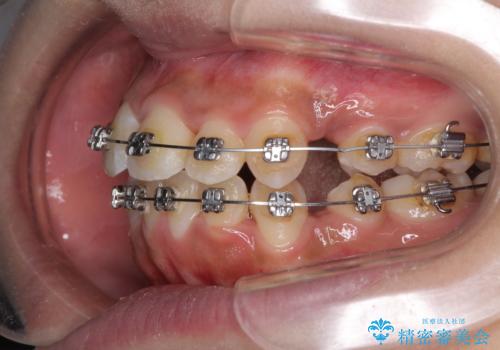

- メタルブラケット

- 2年1ヶ月

- 10-30回

上下前歯部叢生のスペース獲得のため、上下顎左右小臼歯各1歯(計4本)と全ての親知らずを抜歯して、矯正治療を行うこととしました。

上下の正中位置が大きくずれていたため、治療期間の長期化や正中が合わないまま終了することが予想されましたが、思っていた以上にスムーズに歯が移動し、満足いただける仕上がりとなりました。